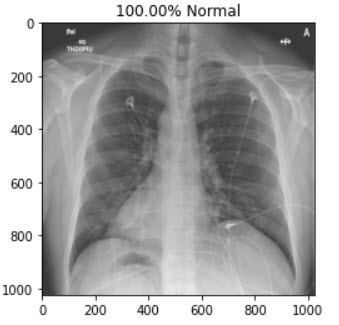

This is a demonstration of a cloud based AI Web Application which helps medical professionals or diagnostic centers to quickly screen/diagnoise the patient in just a single click.

I've teamed up with AI enthusiasts and got inspired from the several news articles to create a end to end web application using Deep learning.We have collected datasets from Mendeley and Qatar University which were posted on kaggle website.We augumented the images and trained the model to detect the hidden patterns in the images and using "Transfer Learning" approach we have used the model to deploy it on cloud platform and hooked it via flask server.

I'm proud that I've built an application for the masses leveraging AI and cost effective and is available to everyone through internet. The overall user experience and performance is exceptional with best results